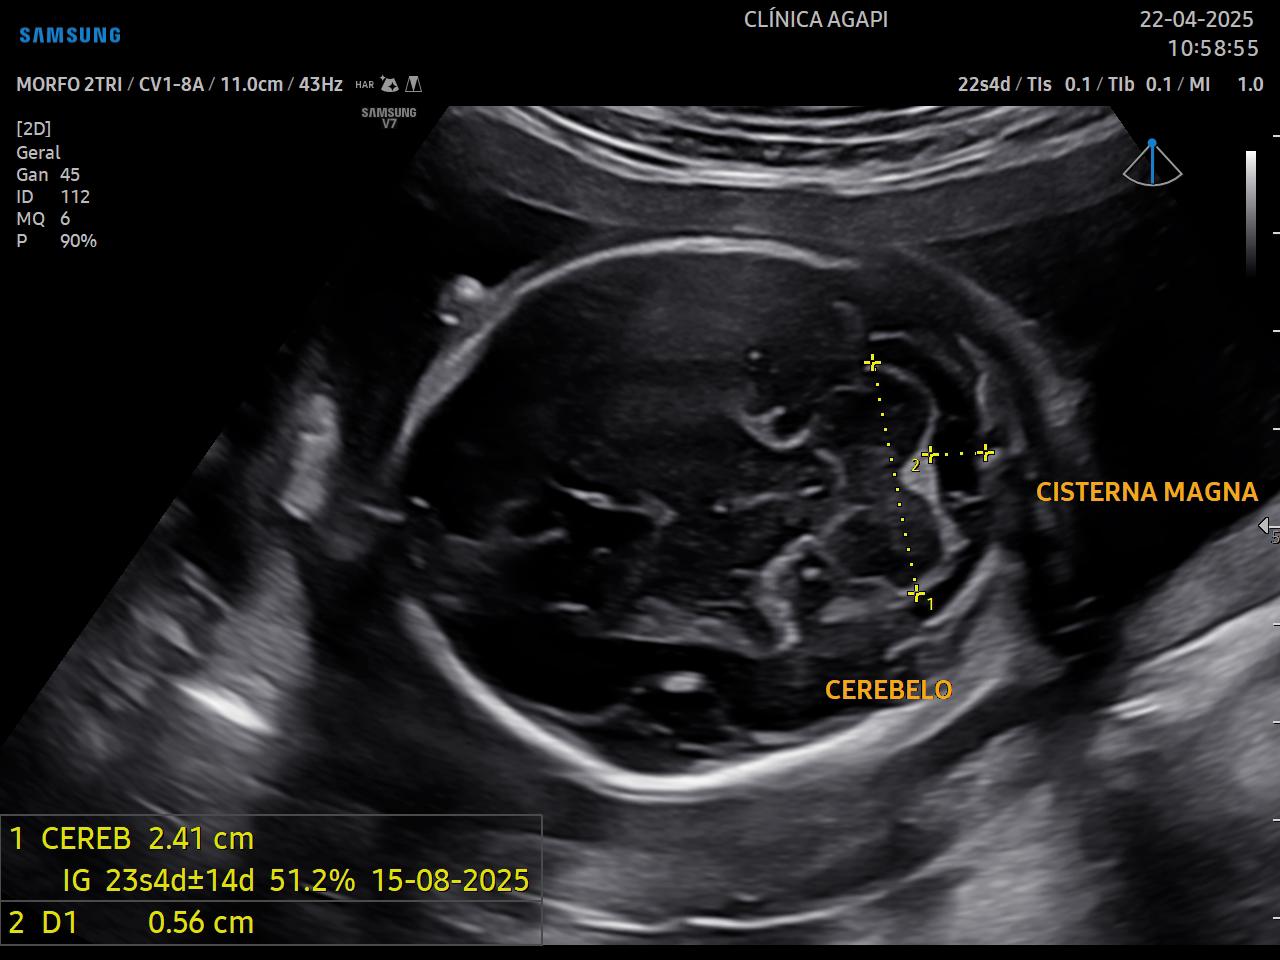

Realizado preferencialmente entre 20 e 24 semanas de gestação, seu objetivo principal é avaliar a anatomia fetal de forma detalhada e detectar possíveis malformações.

Aqui, o exame é sempre completo, incluindo o transvaginal e o doppler das artérias uterinas.